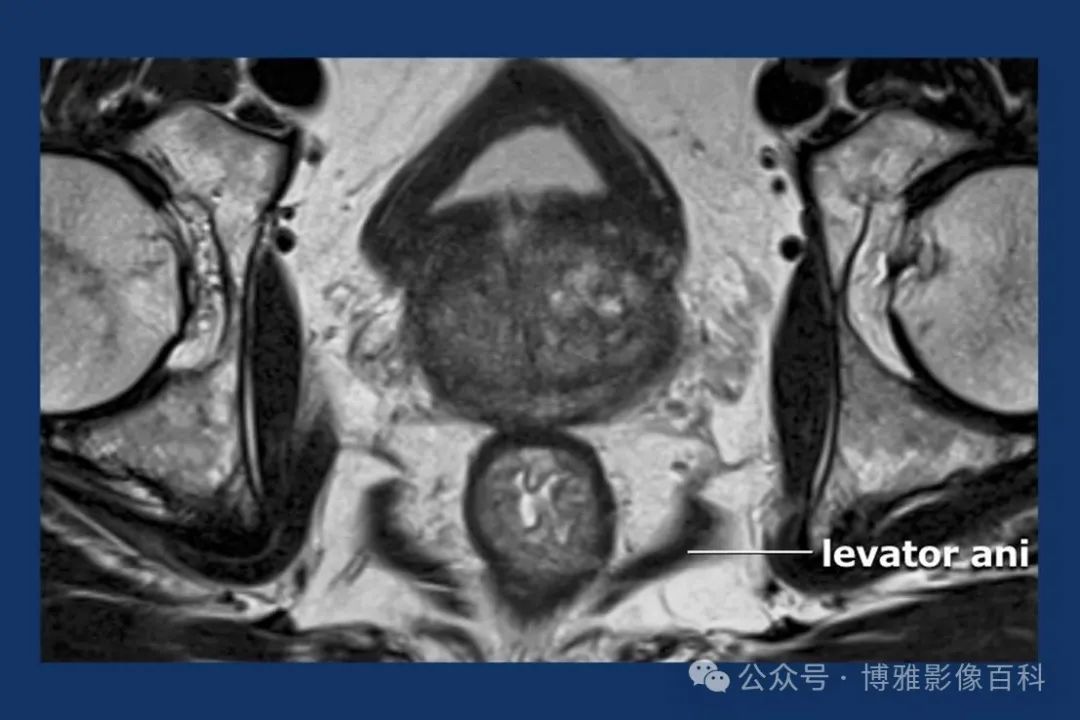

MR 解剖学

前列腺良性增生患者的轴向T2 图像,其他方面正常。外周带是一薄层均匀的高信号,边界清晰连续性的低信号包膜。移行带通常表现为不均匀中等信号,病灶被边界清楚的BPH良性前列腺增生结节所取代。精囊具有均匀T2高信号。未见淋巴结肿大。